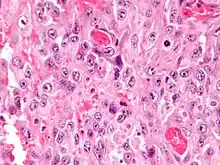

Micrograph of an epithelioid sarcoma. H&E stain.

Histologically, epithelioid sarcoma forms nodules with central necrosis surrounded by bland, polygonal cells with eosinophilic cytoplasm and peripheral spindling.[3] Epithelioid sarcomas typically express vimentin, cytokeratins, epithelial membrane antigen, and CD34, whereas they are usually negative for S100, desmin, and FLI1 (FLI-1).[3] They characteristically lack the protein INI1 (see below). Epithelioid sarcomas typically stain positive for CA125.[4]